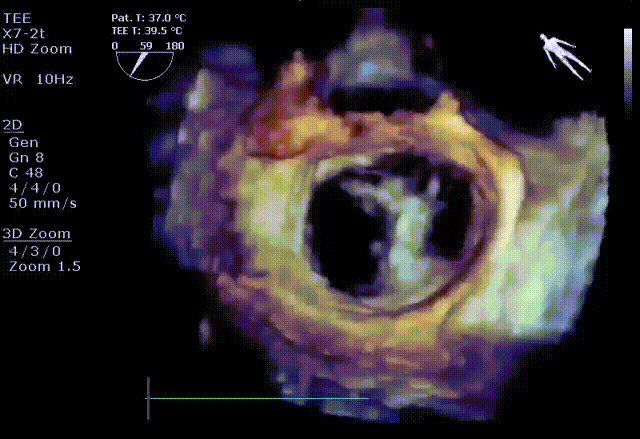

在阜外医院潘湘斌教授团队的支持下,手术经股静脉-房间隔入路,采用全身麻醉插管,在TEE和DSA引导下完成房间隔穿刺。置入JensClip瓣膜夹系统后,在左房调整瓣膜夹的位置和轴向,后进入左室,在TEE引导下捕捉二尖瓣前后瓣叶,并关闭瓣膜夹。经TEE反复确认手术效果后最终锁定并释放瓣膜夹。术后即刻超声显示瓣膜夹位置稳定,功能良好,二尖瓣反流由术前4+减少至微量,手术圆满成功。

术后超声